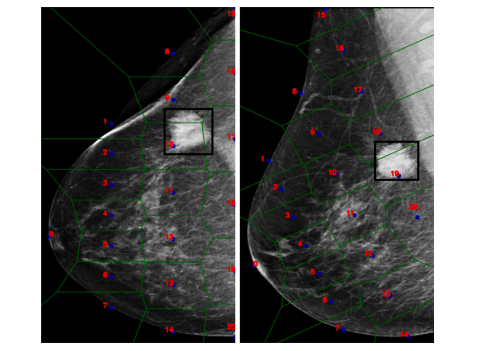

Fig. 2. A representation of pseudo-landmark and the respective tessellation of the samebreast in the two projections.

图2. 伪标志点的表示及其在同一乳房的两个投影中的相应镶嵌分布。

Fig. 3. A representation of the entire AGN4V model. It is worth noting that thisarchitecture requires an additional set of inputs (that is, the pseudo-landmarks andtheir position), which are used by the IGN and BGN modules to simulate radiologists’analysis.

图3. 整个AGN4V模型的表示。值得注意的是,该架构需要一组额外的输入(即伪标志点及其位置),这些输入由IGN和BGN模块使用,以模拟放射科医生的分析过程。